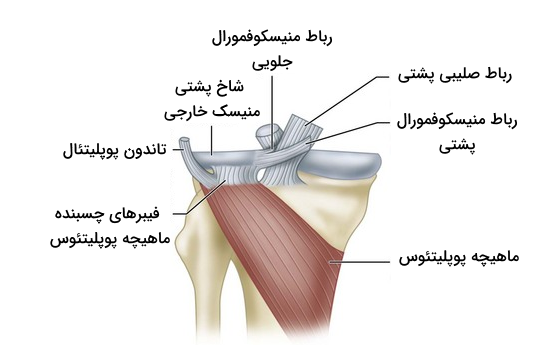

رباط پوپلیتئال مایل

رباط پوپلیتئال مایل که به نام «رباط بورژری» (Bourgery Ligament) نیز شناخته میشود، حاصل گسترش تاندون نیمغشایی است. این رباط از ناحیه پشتی کوندیل داخلی درشتنی منشأ میگیرد و به صورت مایل به سمت بالا و خارج کشیده میشود تا به کوندیل خارجی استخوان فمور متصل شود. این رباط با عبور از حفره بین کوندیلی قادر به تقویت بخش پشتی کپسول مفصل است. در نهایت رباط پوپلیتئال مایل به بخش مرکزی کپسول مفصل می پیوندد.

رباط پوپلیتئال قوسی

رباط پوپلیتئال قوسی نواری ضخیم و فیبری است که از بخش پشتی سر استخوان نازکنی منشأ میگیرد و به صورت قوسی به سمت بالا و داخل حرکت میکند تا به بخش پشتی کپسول مفصل زانو متصل شود. این رباط بخش جانبی پشت کپسول مفصل زانو را تقویت میکند و همراه با رباط پوپلیتئال مایل، از کشیدگی بیش از حد مفصل زانو جلوگیری میکند.

رباطهای نگهدارنده منیسکهای زانو

رباطهای زانو به مواردی که تا اینجا یاد گرفتیم محدود نمیشوند. در بررسی آناتومی زانو با رباطهایی مواجه میشویم که مسئولیت حفظ موقعیت مکانی منیسکهای زانو را برعهده دارد. در ادامه بخشی خاص را به آشنایی با منیسکها اختصاص میدهیم، اما به طور کلی باید گفت که آنها ساختارهایی در سطوح مفصلی هستند که در تطابق مفاصل دو استخوان فمور و درشت نی و ضربهگیری نقش دارند. رباطهایی که منیسکها را در جای خود نگه میدارند، شامل موارد زیر هستند.

- «رباط عرضی» (Transverse Ligament)

- «رباطهای منیسکوفمورال» (Meniscofemoral Ligaments)

- «رباطهای منیسکوتیبیال» (Meniscotibial Ligaments)

این رباطها با تثبیت منیسکها به طور غیرمستقیم در جلوگیری از جابهجایی مفصل زانو نقش دارند، بنابراین در ادامه توضیحات بیشتری در مورد هر کدام ارائه میدهیم.

رباطهای منیسکوفمورال

رباطهای منیسکوفمورال در بخش بالایی انتهای دیستال رباط طرفی داخلی قرار دارند. این رباطها شاخ پشتی منیسک خارجی را به بخش خارجی کوندیل داخلی استخوان ران متصل میکنند. این رباطها به دو نوع زیر تقسیم میشوند.

- «رباط منیسکوفمورال جلویی» (Anterior Meniscofemoral Ligament): این رباط از جلوی رباط صلیبی پشتی عبور میکند.

- «رباط منیسکوفمورال پشتی» (Posterior Meniscofemoral Ligament): این رباط از پشت رباط صلیبی پشتی عبور میکند.